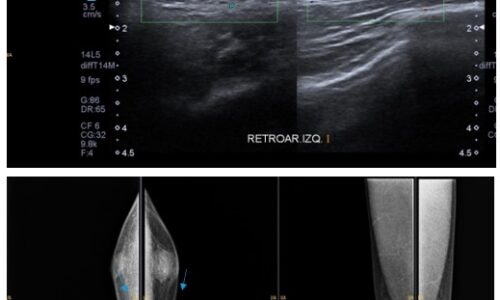

Meningioma del nervio óptico. Hallazgo ecográfico incidental

El meningioma primario de la vaina del nervio óptico es un tumor raro, cuyo manejo diagnóstico y terapéutico ha variado de manera sustancial en los últimos años. Se trata de tumores inusuales de la vía visual anterior (…)